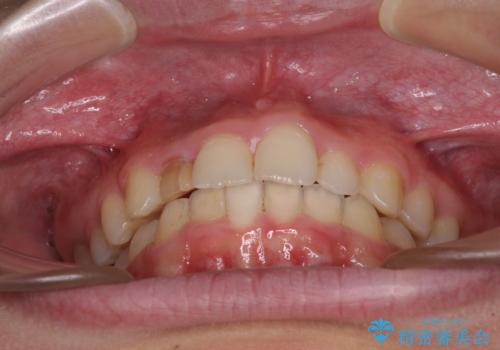

- 前歯の歯並びと不自然な色をした前歯のクラウンを気にして来院された患者様です。

上下前歯の歯列不正はインビザラインにより歯列を整え、その後に、前歯をオーダーメイドタイプのオールセラミッククラウンにて補綴治療することとしました。

前歯のデコボコを一番気にしていらっしゃいましたが、矯正治療により下顎前歯が隠れるほどのディープバイトも一緒に改善され、奥歯に負担のかかりにくい咬み合わせとなりました。